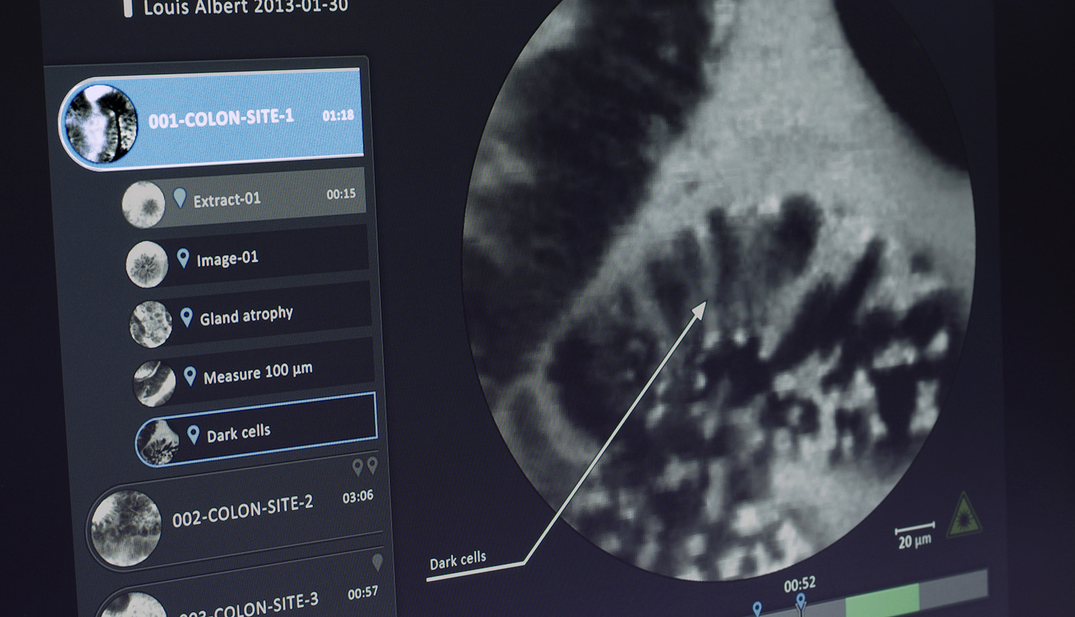

Cellvizio® est un appareil novateur qui permet de détecter des tumeurs cancéreuses avec une grande précision grâce a un système basé sur une minisonde, couplée à une imagerie microscopique.

L’enjeu principal du design a été de concilier sur un même écran la visualisation des séquences transmises par la sonde avec les nouveaux outils conçus pour accompagner le gastroentérologue dans sa procédure médicale.

• Faciliter la lecture et la compréhension de l’imagerie microscopique grâce à une base de données de référence composée d’images et de vidéos (atlas) ;

• Trier et d’annoter les images clés de sa procédure (movie-splitter, annotations fléchées) ;